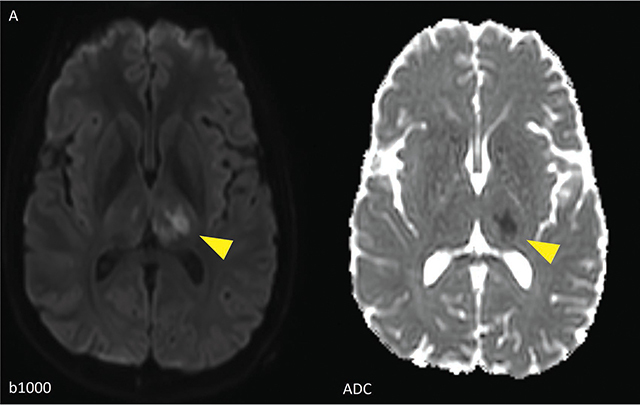

Teaching point: Meningovascular neurosyphilis is a cause of stroke in the young, and the diagnosis could be aided by black-blood MRI sequences.

教学要点:脑膜血管神经梅毒是导致年轻人中风的原因之一,黑血磁共振成像序列可以帮助诊断。